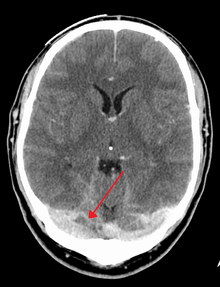

Cerebral venous sinus thrombosis (CVST) is the presence of acute thrombosis (a blood clot) in the dural venous sinuses, which drain blood from the brain. Symptoms may include headache, abnormal vision, any of the symptoms of stroke such as weakness of the face and limbs on one side of the body, and seizures. The diagnosis is usually by computed tomography (CT/CAT scan) or magnetic resonance imaging (MRI) employing radiocontrast to demonstrate obstruction of the venous sinuses by thrombus.[1]

There are various neuroimaging investigations that may detect cerebral sinus thrombosis. Cerebral edema and venous infarction may be apparent on any modality, but for the detection of the thrombus itself, the most commonly used tests are computed tomography (CT) and magnetic resonance imaging (MRI), both using various types of radiocontrast to perform a venogram and visualise the veins around the brain.[1]

Computed tomography, with radiocontrast in the venous phase (CT venography or CTV), has a detection rate that in some regards exceeds that of MRI. The test involves injection into a vein (usually in the arm) of a radioopaque substance, and time is allowed for the bloodstream to carry it to the cerebral veins - at which point the scan is performed. It has a sensitivity of 75-100% (it detects 75-100% of all clots present), and a specificity of 81-100% (it would be incorrectly positive in 0-19%). In the first two weeks, the "empty delta sign" may be observed (in later stages, this sign may disappear).[5]